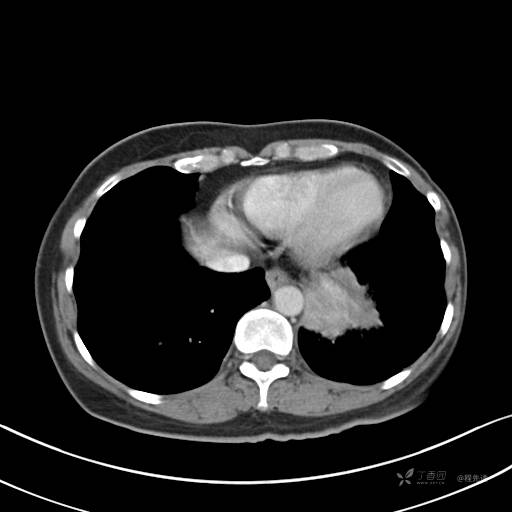

增强静脉期

静脉期CT值约84HU